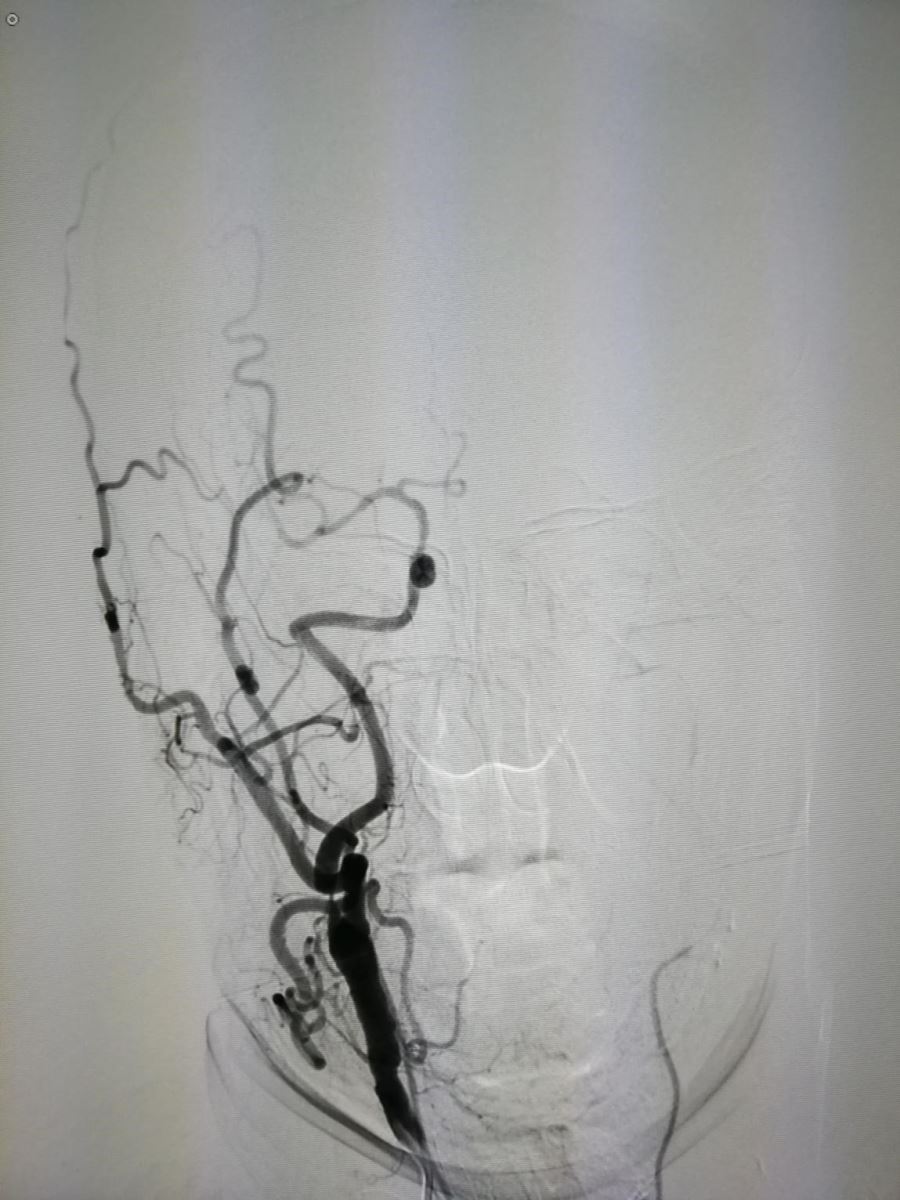

如果单看颅内血管成像,无需介入治疗,但如果连同颈部动脉血管成像(图2、3)。

图2 图3

则患者有必要行血管内支架植入治疗(2018-09-12为该患行支架植入治疗)。图4为术后正位,图5为正位支架位置。